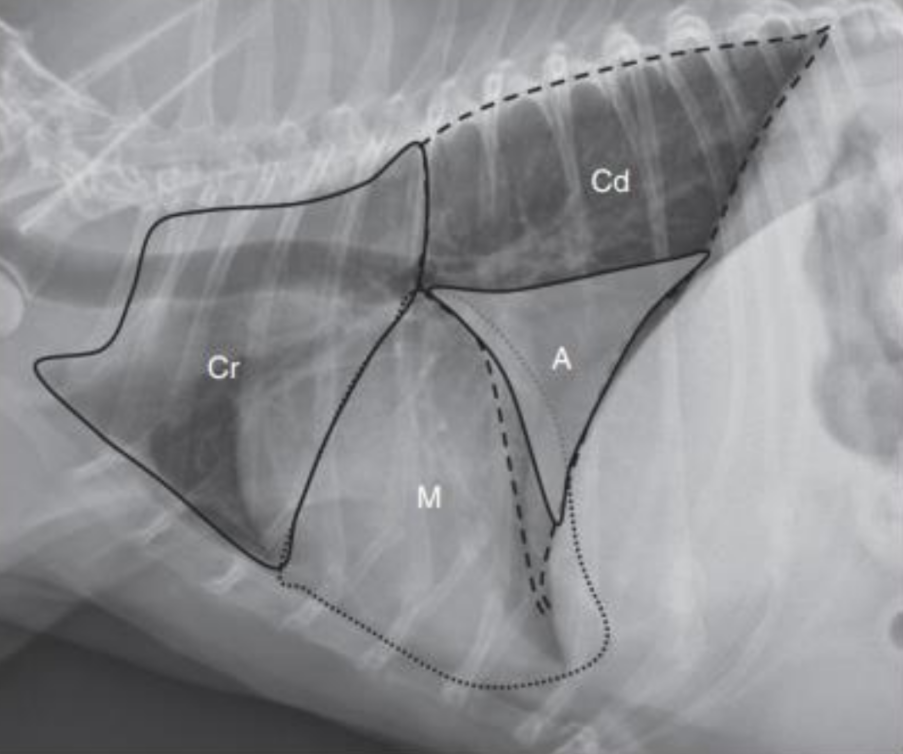

1. Normal Anatomy

| Thorax | |